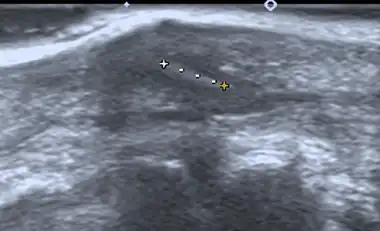

Imaging

If manual detection and localization fail, the main methods for medical imaging of splinters are:

- Medical ultrasonography – used to locate glass, metal, pencil graphite, some plastics, stone, and some types of wood.[6]

Small wooden splinters (1–4 mm) distant from bones are most easily detected by ultrasonography, while CT scan and magnetic resonance imaging have higher sensitivity for those near bones.[7]